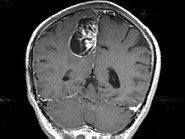

- 单项选择题男,68岁, 头痛头昏、左侧肢体肌力减退3个月余,请根据所提供图像, 选择最可能的诊断是 ( )

A、(右顶叶镰旁)血管外皮瘤

B、(右顶叶镰旁)转移瘤

C、(右顶叶镰旁)脑膜瘤(血管瘤型)

D、(右顶叶镰旁)胶质瘤

E、(右顶叶镰旁)恶性脑膜瘤